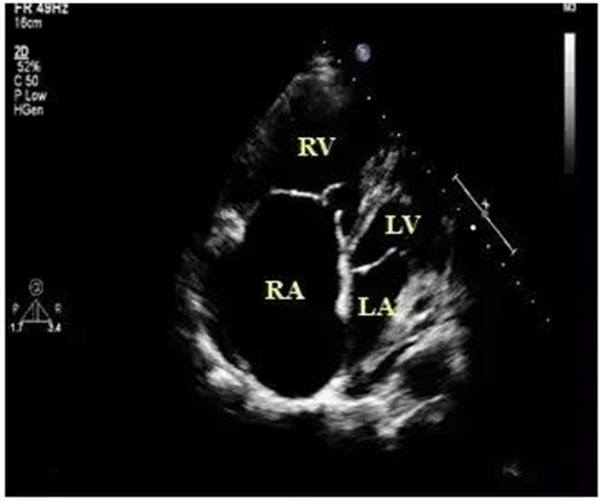

作为最特异的超声心动图特征,当右室/左室前后径比值 > 0.5;右室/左室横径(右房/左房横径)比值 >1.1或者左心室收缩末期和舒张末期径均减小,尤以舒张末期为著时,即可判定血栓性肺栓塞症。

上图:

右室壁运动幅度减低

正常情况下,右室前壁运动幅度应>5 mm,右室游离壁运动幅度会>8 mm,但对肺栓塞(PTE)患者,右室壁基底部至游离部运动幅度减低,甚至消失。